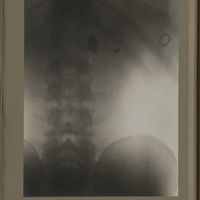

0117 - Page 5 - [Radiographie du bassin]0117 - Page 5 - [Radiographie du bassin]

0128 - Page 16 - [Radiographie du bassin]0128 - Page 16 - [Radiographie du bassin]

0167 - Page 55 - [Radiographie du bassin]0167 - Page 55 - [Radiographie du bassin]